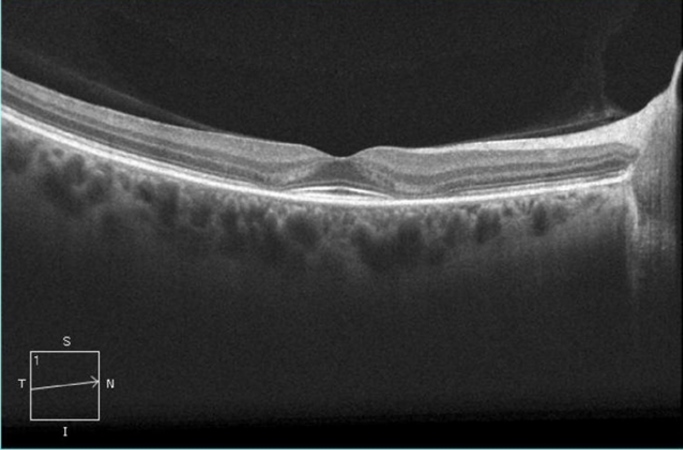

La imagen clínica característica clásicamente ha sido una maculopatía bilateral en “ojo de buey” una apariencia causada por un anillo parafoveal de despigmentación del EPR que excluye la zona foveal central. De cualquier forma este patrón ya no debería ser visto, ya que las recomendaciones actuales podrían detectar toxicidad antes de un daño visible en el examen del fondo de ojo, el cual es irreversible.

Se recomienda el uso de campos visuales automatizados y la OCT de dominio espectral, para el cribado rutinario primario ya que estos están ampliamente disponibles. Los campos visuales son altamente sensibles y confiables, el patrón de campo 10-2 tiene una alta resolución dentro de la macula. La OCT de dominio espectral muestra un adelgazamiento de las capas de los fotorreceptores en las regiones parafoveales. Estos adelgazamientos son fuertes indicadores de toxicidad. Otro estudio que puede ser de gran utilidad en casos sospechosos es el electrorretinograma multifocal, el cual genera una respuesta topográfica a través del polo posterior y puede objetivamente documentar una depresión parafoveal en la retinopatía temprana.Actualmente no se recomienda para el cribado la exploración exclusiva de fondo de ojo, angiografía con fluoresceína, el electrorretinograma de campo amplio, rejilla de Amsler, el test de colores.